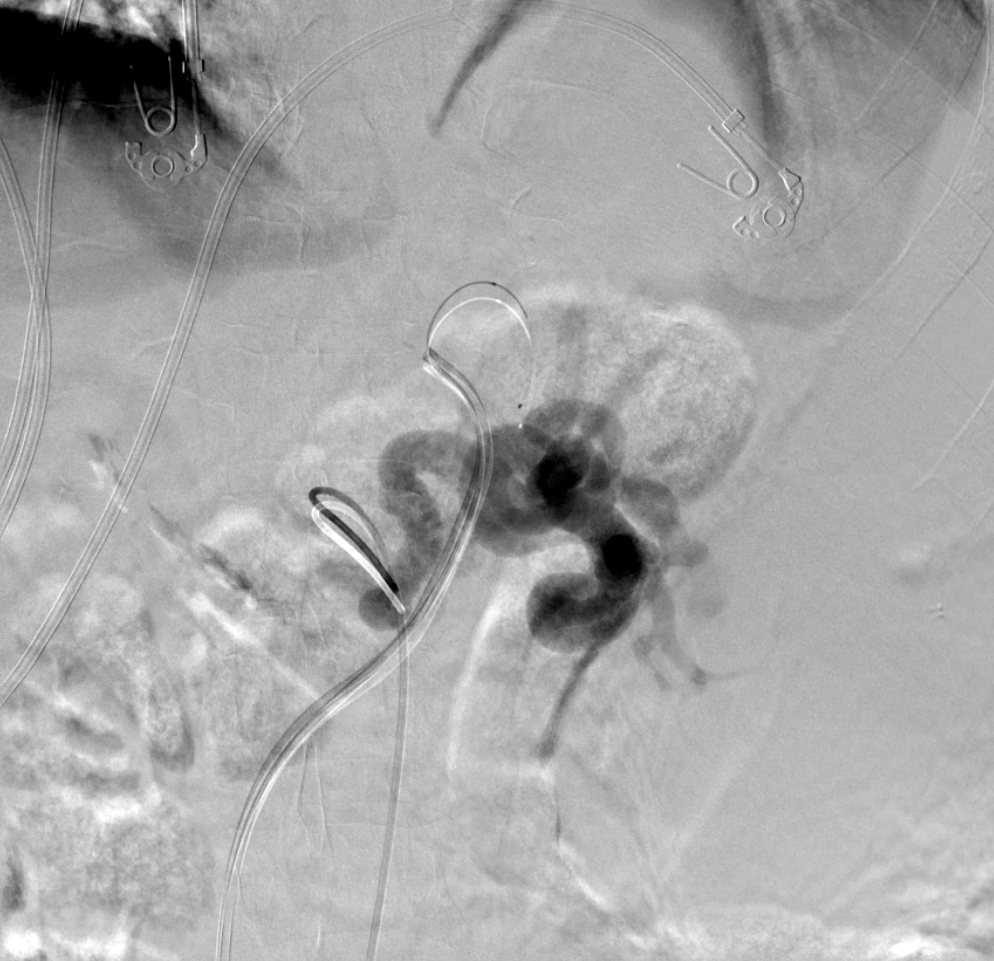

SVC syndrome from Type 4, chronic , CTVO with h/0 lung malignancy EBRT. CT shows both Innominate, SVC occlusion with extensive chest wall collaterals. Done with conscious sedation although prefer GA.

@SIRspecialists@SIR_ECS@JVIRmedia@AVIRnews#irad#Occlusion#SVC@EVTodaypic.twitter.com/iJGNmgePEJ